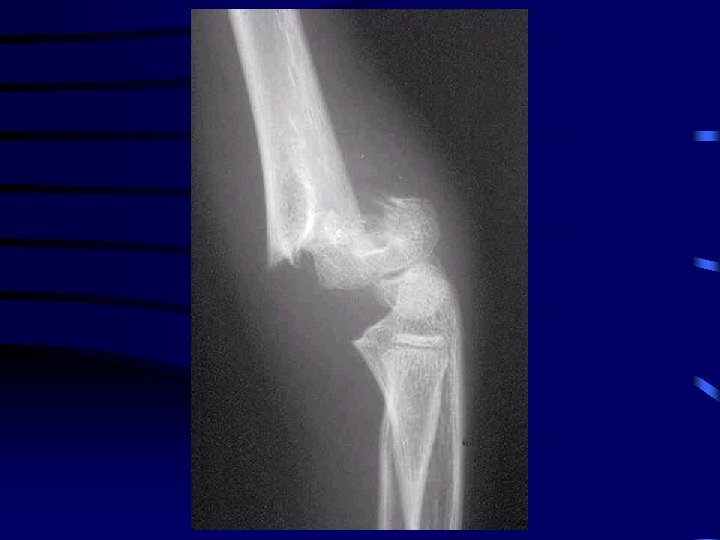

Particularité : le coude • L'examen clinique doit recher : · une atteinte nerveuse : médian (et en particulier l'atteinte du nerf inter-osseux antérieur), radial ou ulnaire · une atteinte vasculaire : recherche du pouls radial • Bilan radio : radiographie du coude Face et Profil

Recherche épanchement